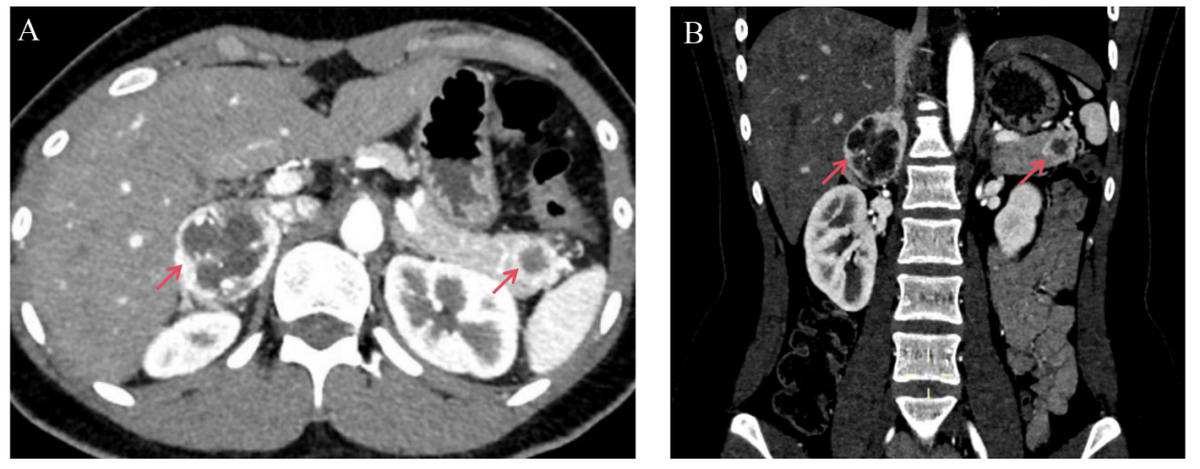

CT 检查结果揭示了更复杂的病情:患者右侧肾上腺存在一个直径约 4 厘米的肿物,结合血清及 24 h 尿儿茶酚胺水平异常升高,提示可能为嗜铬细胞瘤(一种可引发严重高血压的肿瘤);更棘手的是,其胰腺尾部还发现一个 2 厘米的肿物,性质不明,需与转移灶、囊肿、腺瘤及神经内分泌瘤等多种病变鉴别。